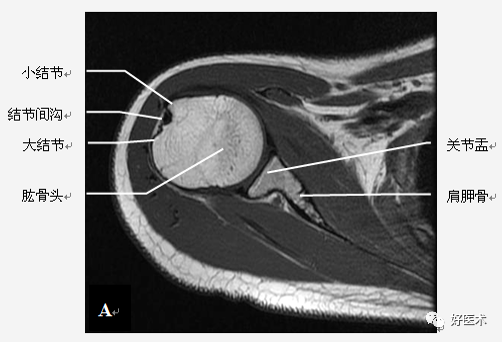

肩关节骨骼构成

三块骨:肩胛骨、锁骨、肱骨

两个关节:

肩锁关节

盂肱关节